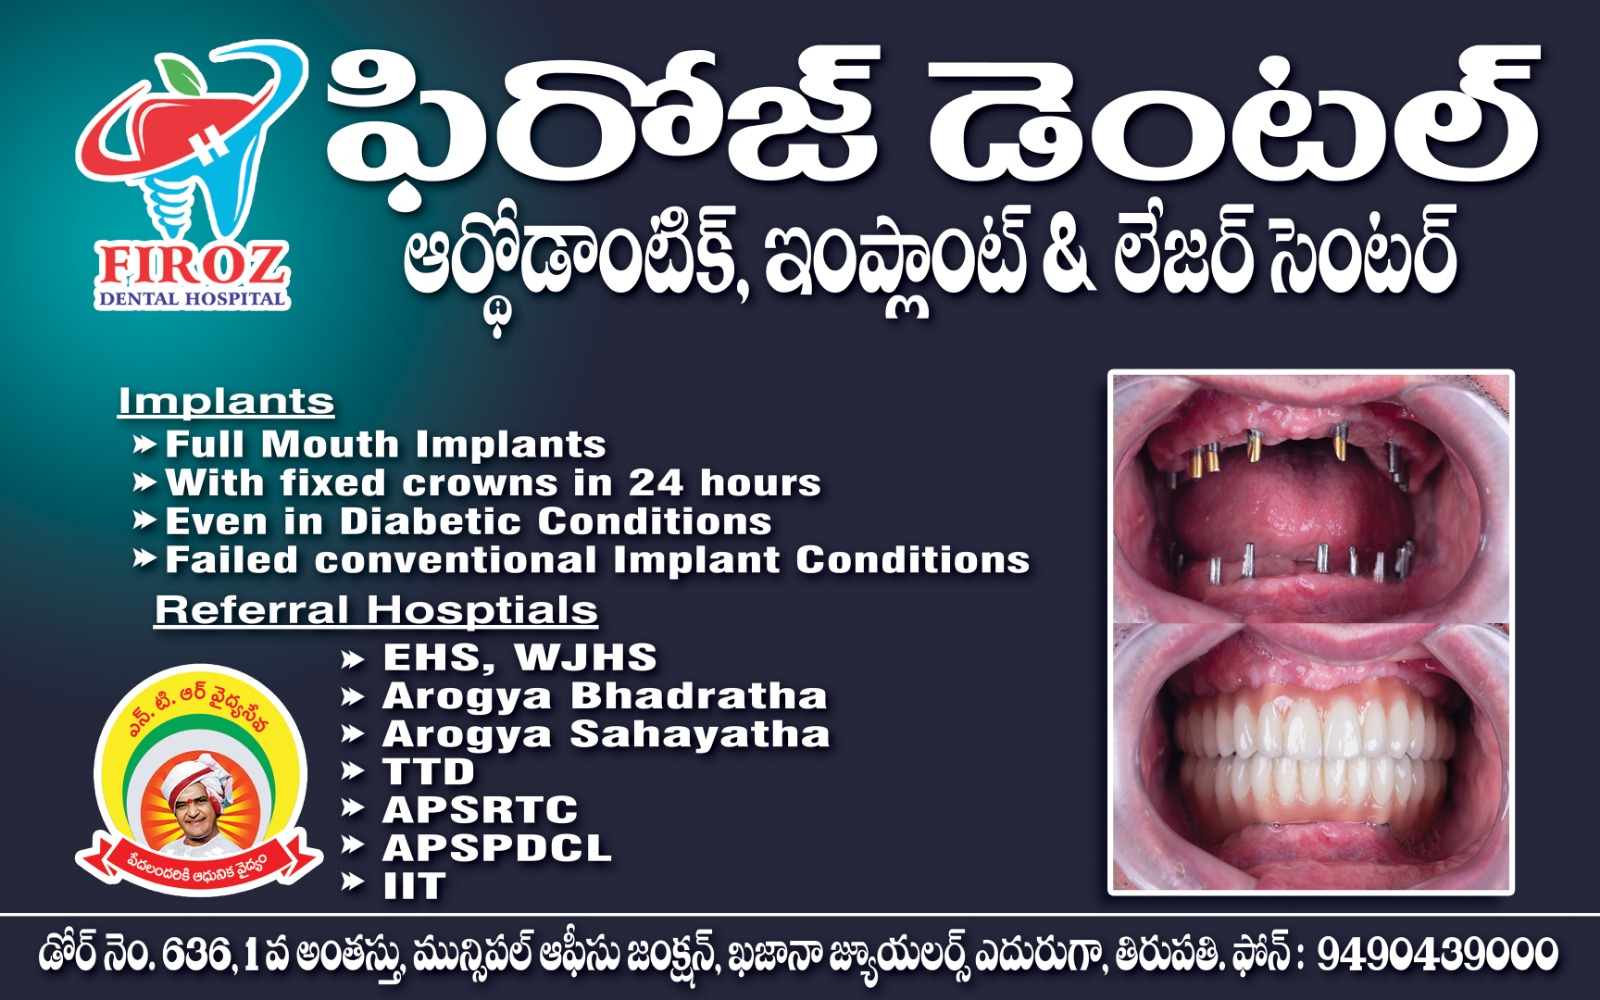

FIROZ DENTAL

Transforming Smiles with Trusted Care – From Braces to Implants, Experience Dental Excellence with Us in Tirupati

We provide comprehensive dental care using modern techniques and advanced technologies. Whether you'... re looking for braces, cosmetic smile corrections, or full-mouth implants, our team delivers precise, comfortable, and long-lasting treatments that restore confidence and oral health. Your smile is in safe hands with our expert dental care professionals. Read more